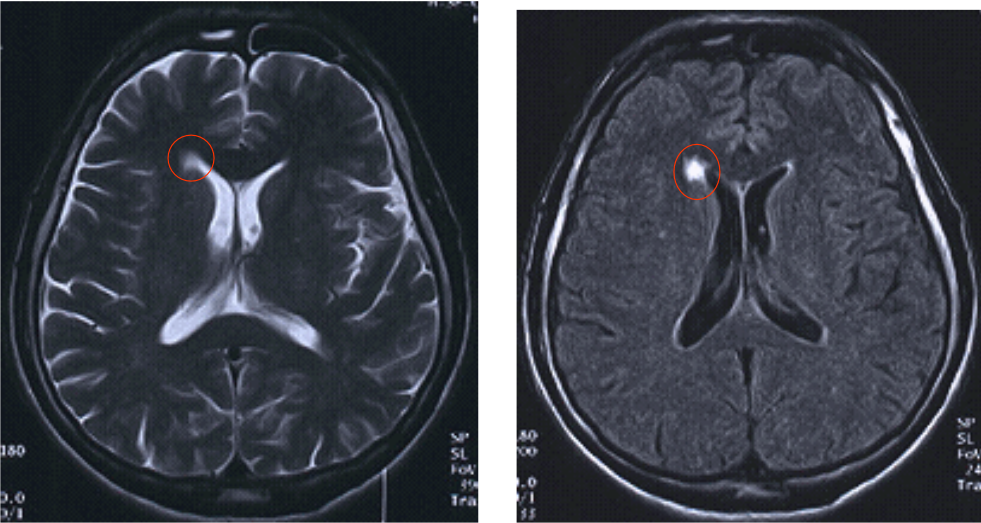

Comparaison T2 et T2 FLAIR